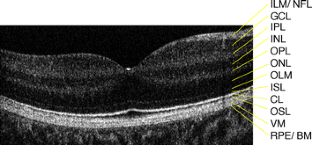

The objective of the paper is to study the retinal microstructure and function in a patient with autosomal recessive bestrophinopathy (ARB). Retinal function and morphology assessment in a patient diagnosed with a biallelic mutation in the BEST1 gene (heterozygote mutations: Leu88del17 and A195V) included: full-field electroretinogram (ffERG) and multifocal electroretinogram (mfERG), electro-oculogram (EOG) testing, and imaging with a high-resolution Fourier-domain optical coherence tomography (Fd-OCT) system (UC Davis Medical Center; axial resolution: 4.5 μm, acquisition speed: 9 frames/s, 1,000 A-scans/frame) combined with a flexible scanning head (Bioptigen Inc.). The 11-year old asymptomatic boy showed a well-demarcated retinopathy with deposits. Functional assessment revealed normal visual acuity, reduced central mfERG responses, delayed rod and rod-cone b-wave ffERG responses, and reduced light rise in the EOG. Fd-OCT demonstrated RPE deposits, photoreceptor detachment, elongated and thickened photoreceptor outer segments, but preserved inner retinal layers. In conclusion, ARB associated retinal dystrophy shows functional and morphological changes that overlap with classic Best disease. For the first time, high-resolution imaging provided in vivo evidence of RPE and photoreceptor involvement in ARB.

Fig. 1

Fig. 2

Fig. 3

Fig. 4